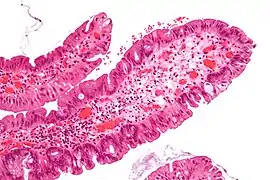

Histopathology

Traditional serrated adenomas are characterized by ectopic crypts, pseudostratification, and a villous pattern with stretched nuclei.[4]